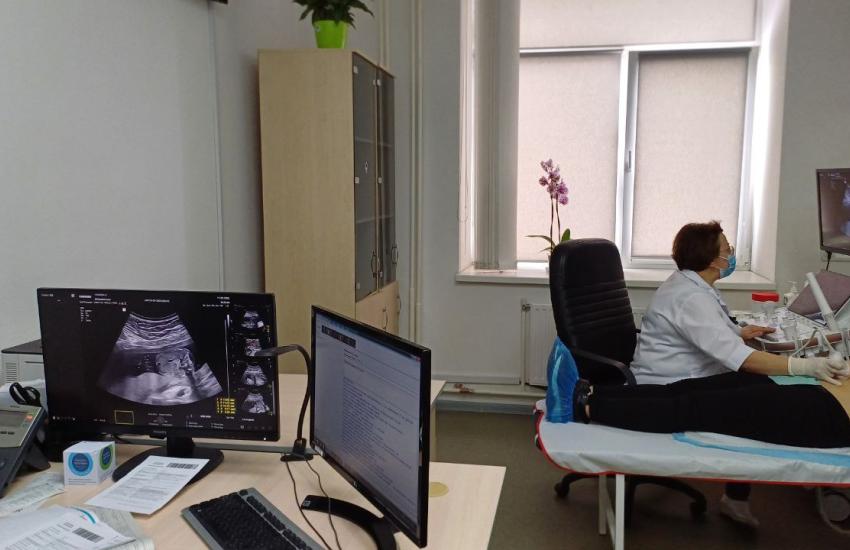

Сучасний УЗД-апарат, яких лише декілька в Україні, запрацював у Черкаському обласному перинатальному центрі

У Черкаському обласному перинатальному центрі нещодавно запрацював УЗД-апарат експертного класу, який дозволить проводити діагностику вагітності на найвищому рівні. Наразі їх лиш декілька на всю Україну.

УЗД-апарат Samsung HERA Z20 у перинатальному центрі встановлений нещодавно, проте вже перші пацієнтки могли відчути його переваги.

Придбали апарат за кошти лікарні. Обійшовся медзакладу він у дев’ять мільйонів гривень. Новий апарат ультразвукової діагностики має низку переваг та безліч нових функцій. Зокрема, це новітня інтелектуальна діагностична система преміум-рівня, створена спеціально для акушерства, гінекології та комплексних обстежень.

- На сьогодні – це найкращий апарат, який може бути, – відзначає лікарка УЗД Оксана Береза. – Наприклад, кардіорежим дозволяє побачити найдрібніші дефекти міжшлуночкової аорти, вихід магістральних судин, ми бачимо особливості будови лівого і правого шлуночків, перехресно-магістральних судин. Також тут є режим, який дозволяє нам бачити дрібні судини. Також дуже високі чутливість апарату та роздільна здатність монітору. Це дає нам можливість побачити найдрібніші особливості розвитку дитини. І наші спеціалісти робитимуть все можливе, щоб бачити якомога більше за допомогою цього УЗД-апарату. Оскільки батьки мають право знати якомога більше про стан їхньої дитини.

Новий УЗД-апарат встановили у поліклінічному відділені перинатального центру, яке розташовується на 3 та 4 поверхах діагностично-консультативного центру.